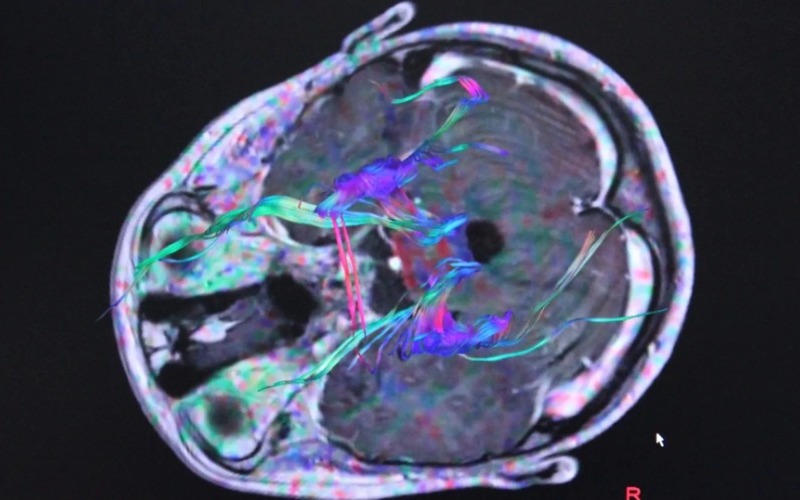

Las células mieloides del intestino detectan estos cambios y su respuesta inflamatoria perjudica la conexión entre el intestino y el cerebro a través del nervio vago.

La buena noticia: los investigadores han comprobado en ratones que si restauran la actividad del nervio vago, también lograr recuperar la función de la memoria de un animal viejo a la de un animal joven, lo que abre prometedoras expectativas para desarrollar tratamientos.

La estimulación del nervio vago en humanos, de hecho, ya está aprobada en muchos países para tratar los síntomas de enfermedades como la epilepsia.

«Nuestro trabajo demuestra que la correcta señalización del intestino al cerebro, a través del nervio vago, protege a los ratones contra el deterioro cognitivo relacionado con la edad», subrayan los autores.